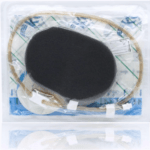

Fasciotomy - Surface VAC

Where shoelaces are not put on or have fallen out a VAC can be used in a 'surface VAC' style to aid in bringing in the skin edges closer together.

Place vac foam

Turn on the machine